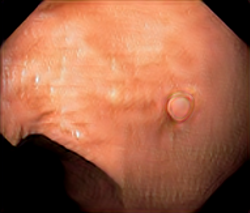

A few sample images and the corresponding masks of the polyp dataset in HyperKvasir are shown in Fig 2. The polyp images are RGB images. The masks of the polyp images are single-channel images with white () for true pixels, which represent polyp regions, and black () for false pixels, which represent clean colon or background regions. In this dataset, there are different sizes of polyps. The distribution of polyp sizes as a percentage of the full image size is presented in the histogram plot in Fig 3, and we can observe that there are more relatively small polyps compared to larger polyps. Additionally, a subset of this dataset was used to prove that the performance of segmentation models trained with small datasets can be improved using our SinGAN-Seg pipeline, and the whole dataset was used to show the effect of using SinGAN-Seg generated synthetic images instead of a large dataset which has enough data to train segmentation models. In this regard, this dataset was used for two purposes:

After training SinGAN-Seg models, we generated random samples per real image using the input scale , which is the lowest scale that uses a random noise input instead of a re-scaled input image. For more details about these scaling numbers and corresponding output behaviors, please refer to the vanilla SinGAN paper [56]. Three randomly selected training images and the corresponding first synthetic images generated using scale are depicted in Fig 4. The first column of the figure represents the real images and the ground truth mask annotated from experts. The rest of the columns represent randomly generated synthetic images and the corresponding generated mask.

In Fig 7, we provide a visual comparison between pure generated synthetic images and style transferred images ( = ). Samples with the style transfer ratio are not depicted here because it is difficult to see the differences visually. The first column of Fig 7 shows the real images used as content images to transfer styles. The rest of the images in the first row of each image shows synthetic images generated from SinGAN-Seg before applying the style transferring algorithm. Then, the images in the second row in the figure show the style transferred synthetic images. Differences of the synthetic images before and after applying the style transfer method can be easily recognized from images of the second reference image (using and rows in Fig 7).